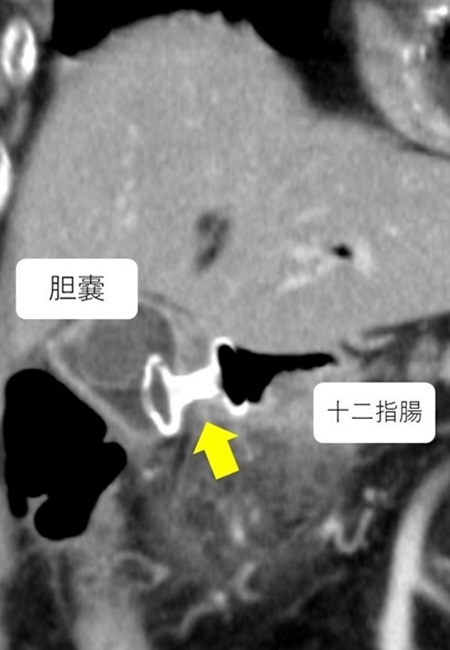

このたび当科では、HotAXIOS systemを用いた内視鏡的胆嚢ドレナージを開始いたしました。本デバイスは、大きなフランジと優れた把持力を有する瘻孔形成用補綴具であり、従来は膵嚢胞などに使用されてきましたが、現在では急性胆嚢炎にも適応されるようになっています。